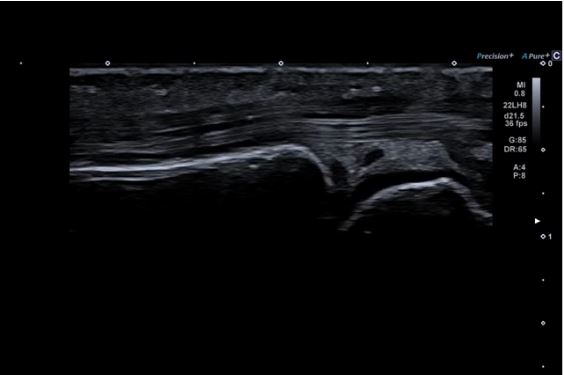

Precision+ Режим точної обробки

Precision+ відомий своєю видатною продуктивністю у створенні однорідних зображень із чіткими контурами, покращеною рівномірністю зображення та зменшенням артефактів. Новий режим Fine Processing Aplio beyond забезпечує ще чистіші зображення з більш чіткими контурами.

Автоматичне вимірювання комплексу інтима-медіа  Auto IMT допомагає підвищити як точність, так і швидкість допплерівських досліджень сонної артерії.

Високочастотний датчик-ключка 22MHz забезпечує деталізацію високої роздільної здатності при дослідженні  п'ястно-фалангового суглоба.

Однорідність структури щитовидної залози демонструється за допомогою лінійного датчика PLU-805BT.